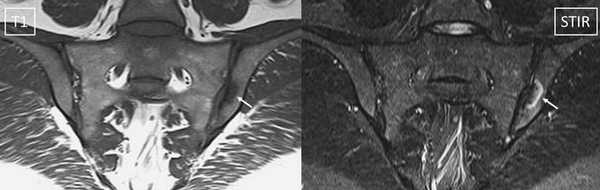

МРТ: симфизит, стрелка указывает на утолщение капсулы, неровность контуров

МРТ-признаки остеомиелита лонных костей: расширение сочленения и скопление жидкости с формированием параартикулярных затеков (длинные стрелки), разрастание грануляционной ткани (короткие стрелки), Т2-ВИ, аксиальная (а) и коронарная (в) плоскости